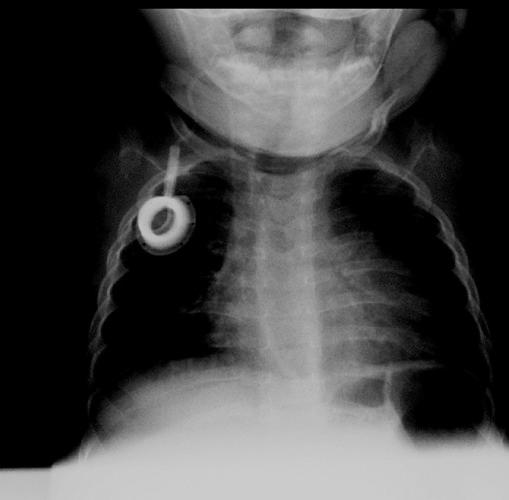

Progress in medical and scientific research has increased the chances of survival for young patients with congenital diseases, children who, in the past, would not have had any chance of survival. Nowadays, congenital diseases can be treated with appropriate replacement therapies. These treatments can be difficult to administer in young patients because of the high frequency of administration (sometimes more than a dose per week), the use of intravenous infusion and the long-term or life-term requirement.

医学和科学研究的进展提高了患有先天性疾病的年轻患者的存活几率,这些儿童在过去没有任何存活的机会。如今,先天性疾病可以通过适当的替代疗法进行治疗。由于给药频率高(有时每周超过一剂)、使用静脉输液以及长期或终身需求,这些治疗在年轻患者中可能难以实施。